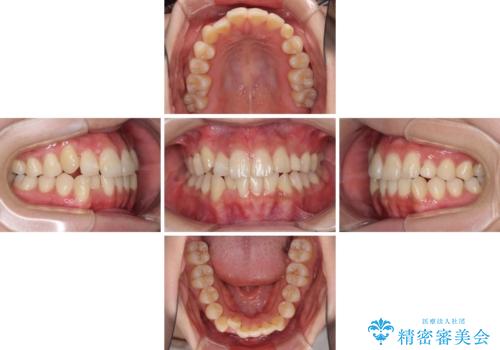

また、インプラント治療については、インビザラインによる矯正治療中の最適なタイミングで治療を行い、治療期間の短縮を図ることとしました。

インプラントは、治療期間を短くすることが可能な、ストローマン社のSLActiveを使用することとしました。

インプラント治療は当初の狙い通り、矯正治療期間中に行い、スムーズに処置を進めることができました。